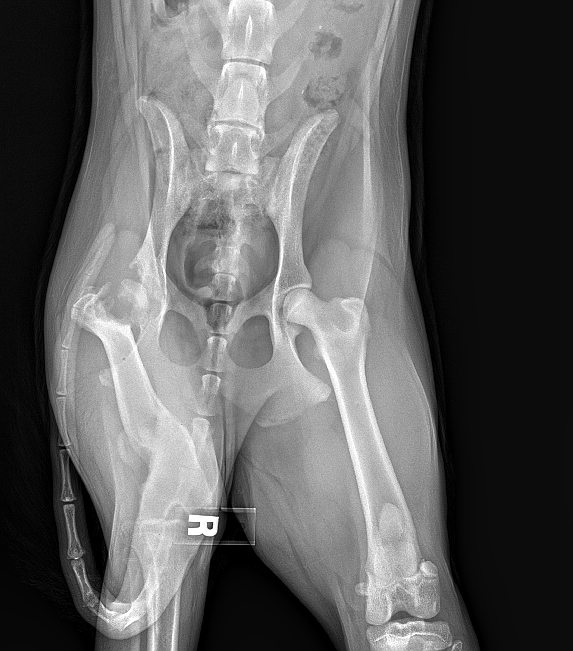

Rescued from the streets in Eastern Wa, Jake came to us with fractures from a broken back leg and musculoskeletal malformations in his front leg. Arthritis is already setting in. We are assuming he was hit by a car but never got taken to a vet for care. So his broken bones and legs healed as they were. Jake has learned how to get around using his back leg very carefully but the fact is he is in pain. His front leg is also of concern so it doesn’t get any worse.

Jake’s pain will need to be closely monitored with treatments and medication. Jake will be extremely limited in what he is able to do but he does a little running and wants to play with other dogs.

We would like to get Jake the continued medical help he needs. He is being seen by surgeon who is kindly offering a free evaluation and exam of Jake's X-rays to determine the best outcome for his care. Every animal we have in our car needs vet care, some more than others.